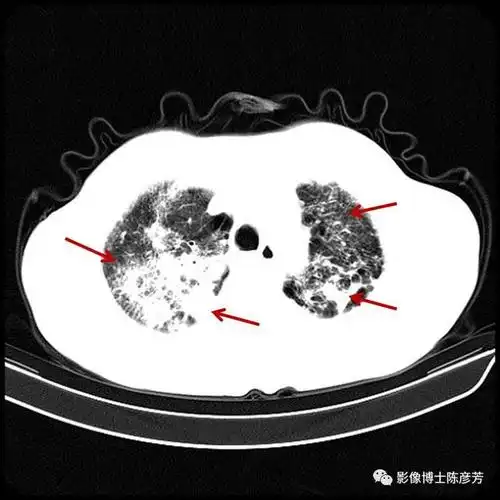

双肺大片的活动性结核病灶.